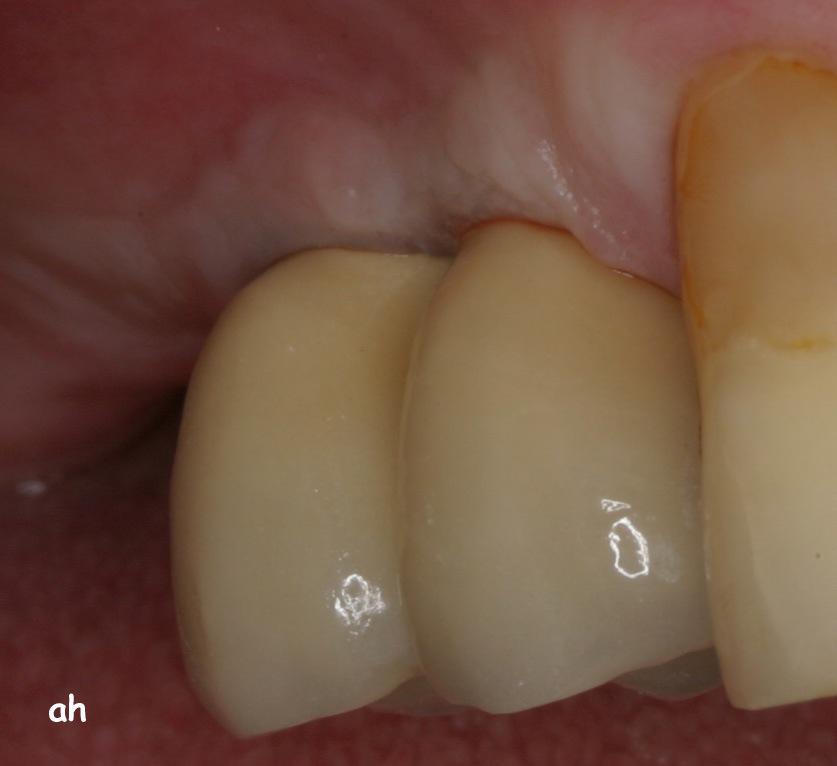

Exemple 11: Après cicatrisation environ 6 mois, le moignon est vissé sur l'implant.

Exemple 11: La couronne céramique en place.